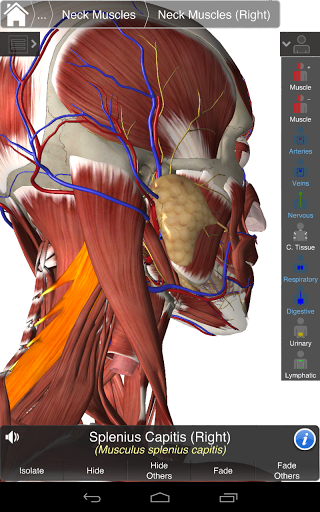

Основна анатомія 3 - це найновіша технологія та новаторський дизайн. Ріжучий 3D-графічний движок, зроблений на замовлення 3D4Medical з усього світу, наділений високоінформативною анатомічною моделлю і забезпечує високу якість графіки, яку не може досягти ніхто інший конкурент.

Програма являє собою унікальний підхід до вивчення загальної анатомії. Графіка не має аналогів і навчається, використовуючи інформативний контент та інноваційні функції, багатий та захоплюючий досвід.

НОВІ 3D-ТЕХНОЛОГІЇ

Основна Анатомія 3 чутлива, візуально приголомшлива і легка. Додаток повністю 3D, що означає, що ви можете переглядати будь-яку анатомічну структуру окремо, а також з будь-якого кута.

Розумна функціональність, знайдена в додатку, дозволяє користувачеві знімати шари м'язів за допомогою інструмента «скальпель». Ця програма надає користувачам можливість увімкнення / вимкнення систем без необхідності скасувати вибір окремих структур або переплутати через безліч попередньо визначених регіональних вкладок, як і інші програми.

---- Більше 4000 дуже детальних анатомічних структур

---- Режим вибору декількох - Сховати / Зменшити / Виділити окремі або кілька структур

---- Правильна аудіо вимова для кожної структури

---- Латинська номенклатура для кожної анатомічної структури